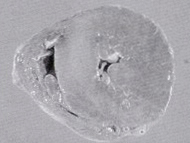

| 脳の動脈(矢印)やはり柔らかい血管で、脳梗塞などはありませんでした | 脳を顕微鏡でみたところ 変性しているアルツハイマーの像(○印)がみられましたが、動脈硬化による脳の変化はありません |